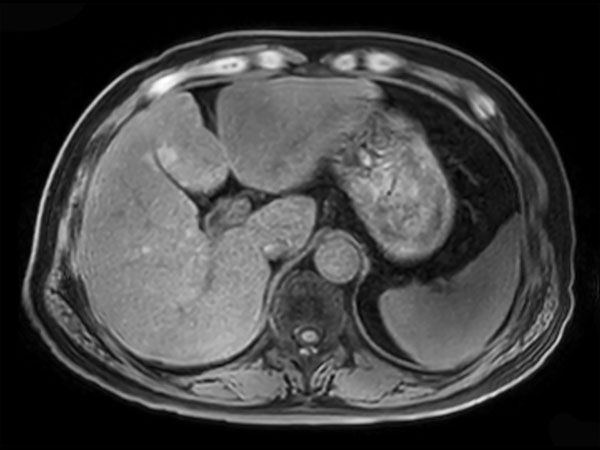

Axial mDIXON XD FFE (Water only)